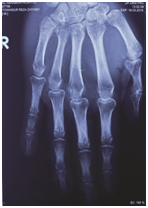

After 1 week the cock-up slab was removed during first follow up. Swelling of Right hand fully subside. Blood circulation intact. Nerve sensation and fingers movements are normal. Encourage finger movements. After 3 weeks both k-wires removed on second follow up. The stability of fifth carpometacarpal joint checked both clinically and radiologically. Also the Indian salutation test was negative. Slight tenderness at fifth carpometacarpal joint with moderate stretch. Encourage both active and passive movement of fingers and wrist joints. After 6 weeks during third follow up, slight tenderness on fifth carpometacarpal joint with deep stretch. All movements of wrist and hand were free. He started motor bike ride. After 3 months, on fourth follow up, the patient regain full functions of injured hand (Right). The grip strength was fully satisfactory (Figure 1–5).

Figure 5 Follow up radiograph after 3 months of reduction.